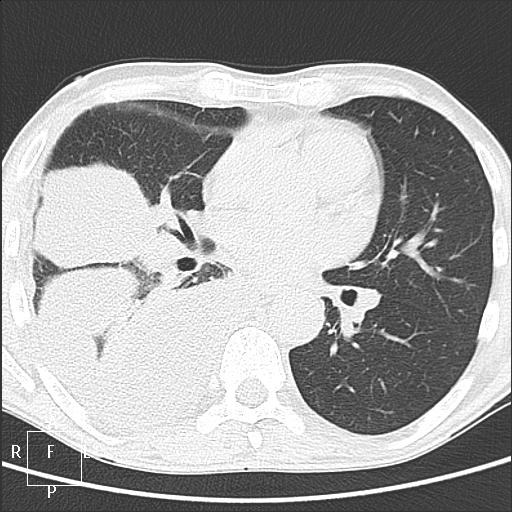

Мужчина 54 года. Слабость и лихорадка неделю. 3 недели назад спленэктомия по поводу тупой травмы живота. Поступает через несколько дней после выписки по "скорой". Дежурит пульмонолог, видит обзорный снимок, берет на бронхоскопию: данных за центральный рак нет.

При поступлении 6.12. дежурным хирургом назначен обзорный снимок ОГК. После которого назначена консультация терапевта. После ФБС пульмонолог назначил боковой снимок. Утром 7.12. описывала оба снимка. Помимо междолевого выпота, не понравилась какая-то странная пневмония в нижней доле. Решила перестраховаться и взять на КТ. Реконструкции (лежа на спине):

smiley По КТ поставила эмпиему. Пункция после КТ по моей метке - гной. Анализ в работе.

В понедельник разузнаю про все анализы, отпишусь. Пневмонии в легких по КТ не нашла, пневмоплеврофиброз справа + массивные осумкованные выпоты, в паракостальном заднем - с пузырьками воздуха и уровнями, бисегментарный компрессионный ателектаз в нижней доле.

Утром 7 декабря я вижу 2 снимка, описываю осумкованные междолевые выпоты, и с учетом не вполне укладывающейся в пневмонию рентгенкартины, с учетом t и цитового анализа крови, беру на КТ. Выставляю эмпиему под вопросом, осумкованные выпоты справа, не вижу патологии со стороны верхнего этажа брюшной полости, ставлю метку для пункции. Через час после КТ пациента пунктируют. После получения в пункции гноя, пациента переводят в отделение гнойной хирургии.